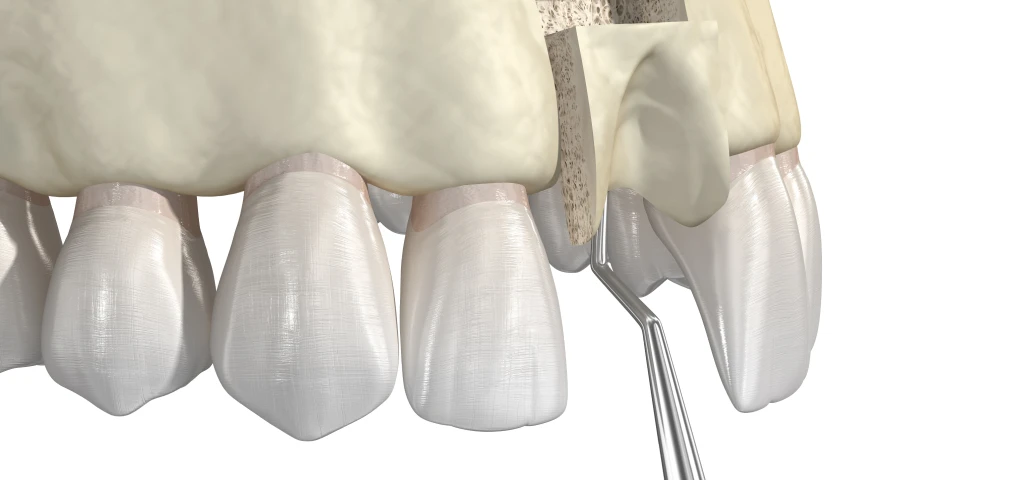

La chirurgie orale regroupe un ensemble d’interventions réalisées au niveau de la bouche, des dents et des mâchoires, allant de l’extraction des dents de sagesse aux actes plus complexes comme les kystes, les freinectomies ou les préparations implantaires.

Au cabinet du Dr Duroux à Cannes, ces actes chirurgicaux sont pratiqués avec rigueur et précision, dans un environnement sécurisé et adapté. L’objectif est d’assurer une prise en charge efficace, en limitant l’inconfort du patient et en favorisant une cicatrisation rapide.